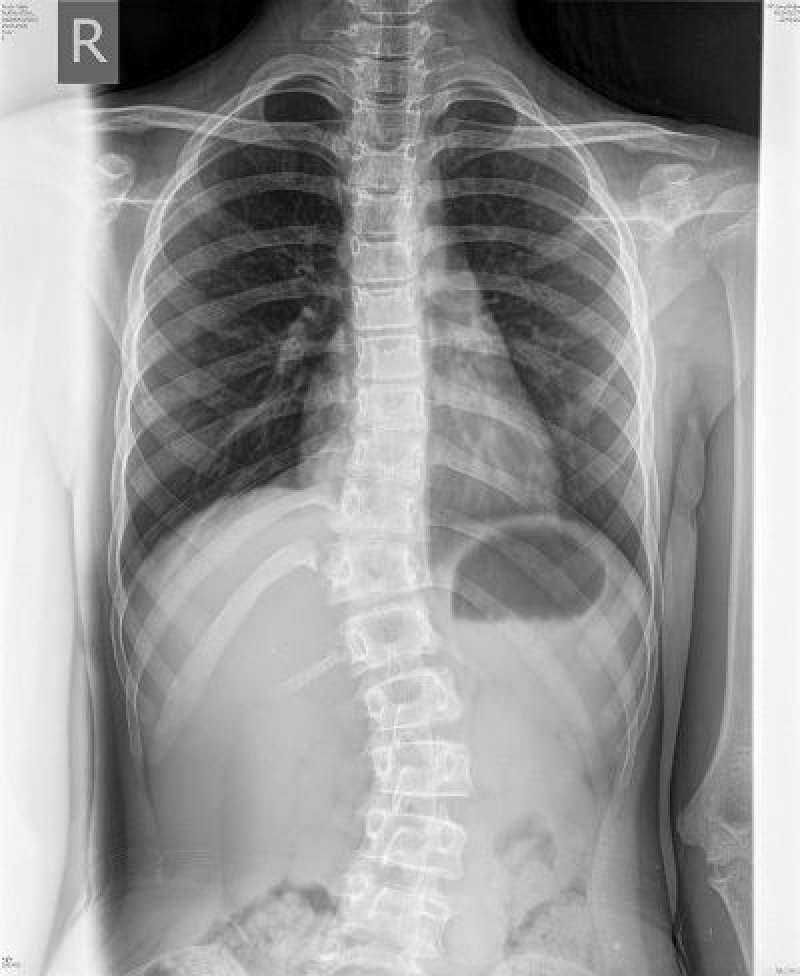

Nejla ima 13 godina, a na KBC Rebro u Zagrebu dijagnosticiran joj je karcinom koji je prouzrokovao skoliozu kičme. Djevojčicu u narednom periodu očekuju dvije teške operacije. Operativni zahvati i ostali troškovi liječenja iznose oko 50.000 KM, zbog čega joj je potrebna naša pomoć kako bi se skupio toliki novac.